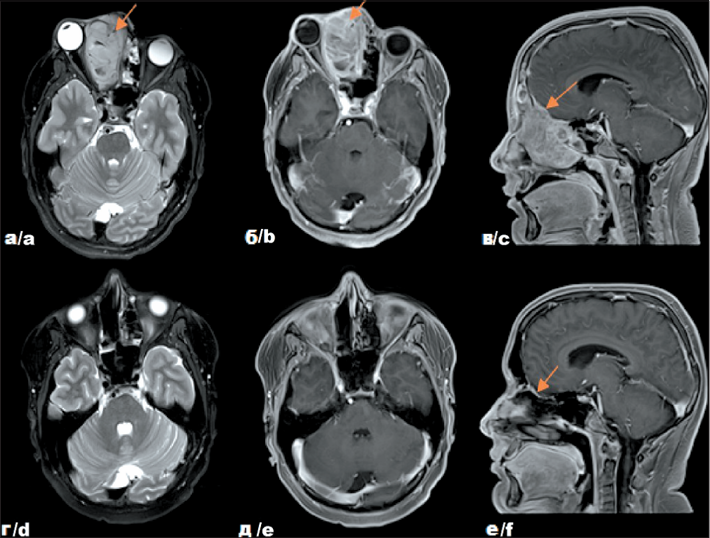

3. Рис. 3. Собственные результаты исследований пациента Р. с диагнозом: Альвеолярная рабдомиосаркома параменингеальной локализации с интракраниальным распространением, метастатическое поражение лимфатических узлов шеи справа, стадия III (T2bN1M0. IRS IIIа), до начала лечения – на томограммах в аксиальной (а) (б) и сагиттальной (в) проекциях и после комбинированного лечения – на томограммах в аксиальной (г) (д) и сагиттальной (е) проекциях. Примечание: рисунок выполнен авторами